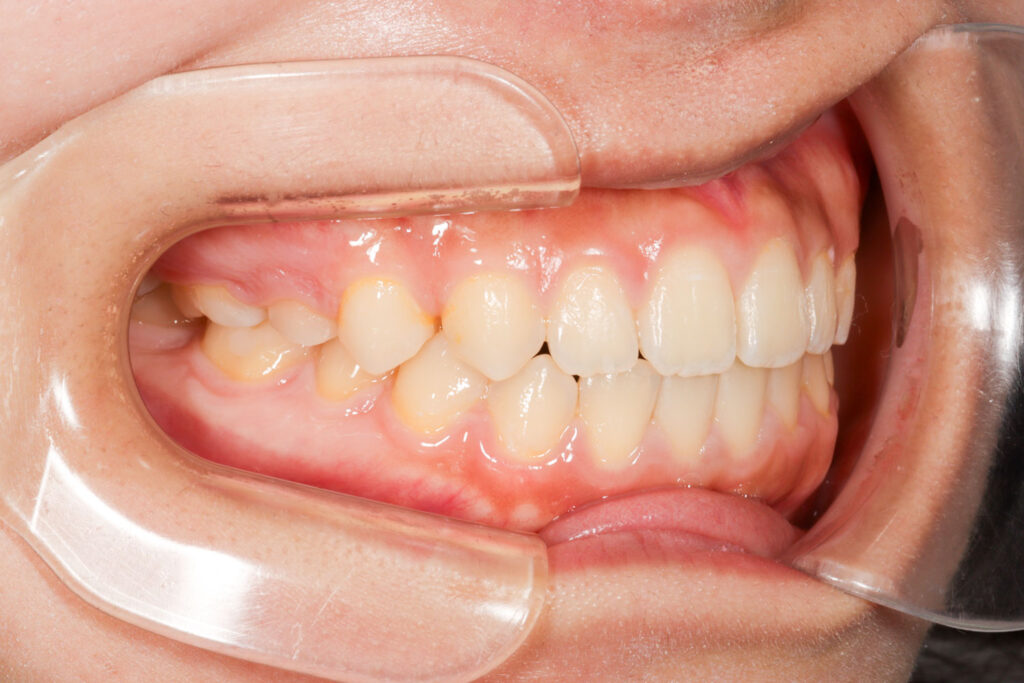

Before

After

年齢 10代

治療装置 上は裏側の矯正装置(フルリンガル)

治療内容 非抜歯

治療期間 2年8か月

リスク 歯の移動に伴う痛み、歯肉退縮、歯根吸収、歯肉炎、虫歯

主訴 ガタガタと隙間が気になる

症状 叢生と正中離開

治療回数 36回程度

総額費用 140万円程度